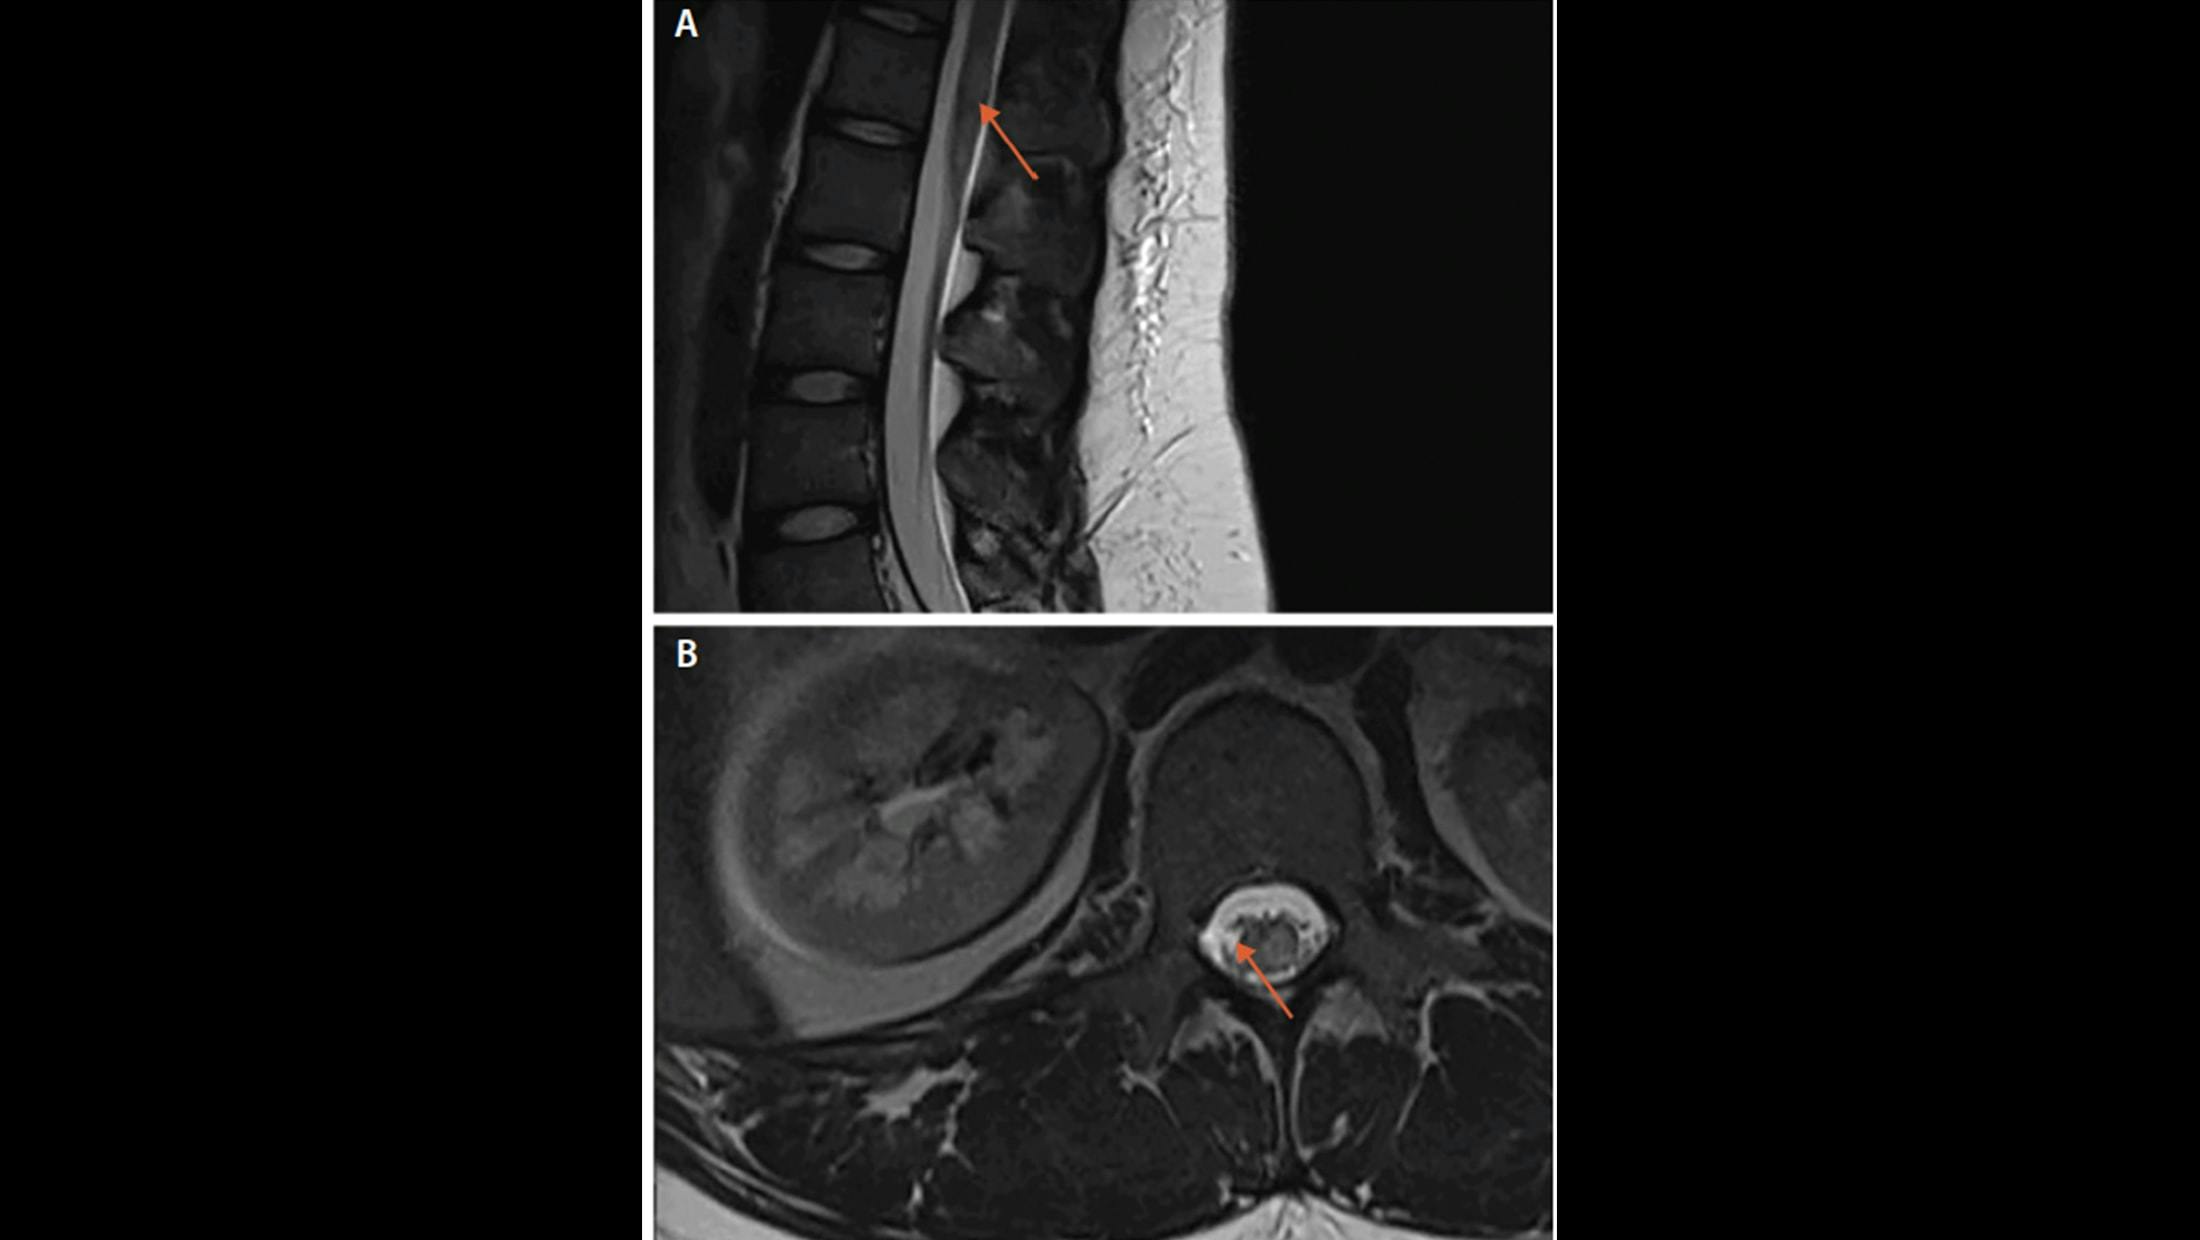

A. Spinal cord lesion in sagittal plane in antimyelin oligodendrocyte glycoprotein (MOG) antibody-associated disease

B. Spinal cord lesion in transverse plane in antimyelin oligodendrocyte glycoprotein (MOG) antibody-associated disease